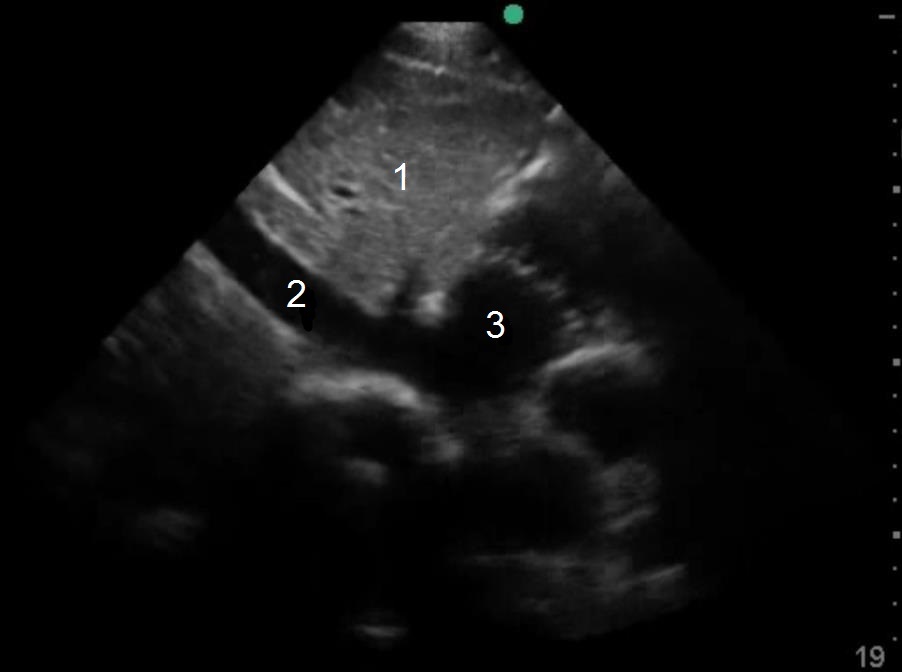

Inferior Vena Cava (IVC) Central Venous Pressure (CVP) Image